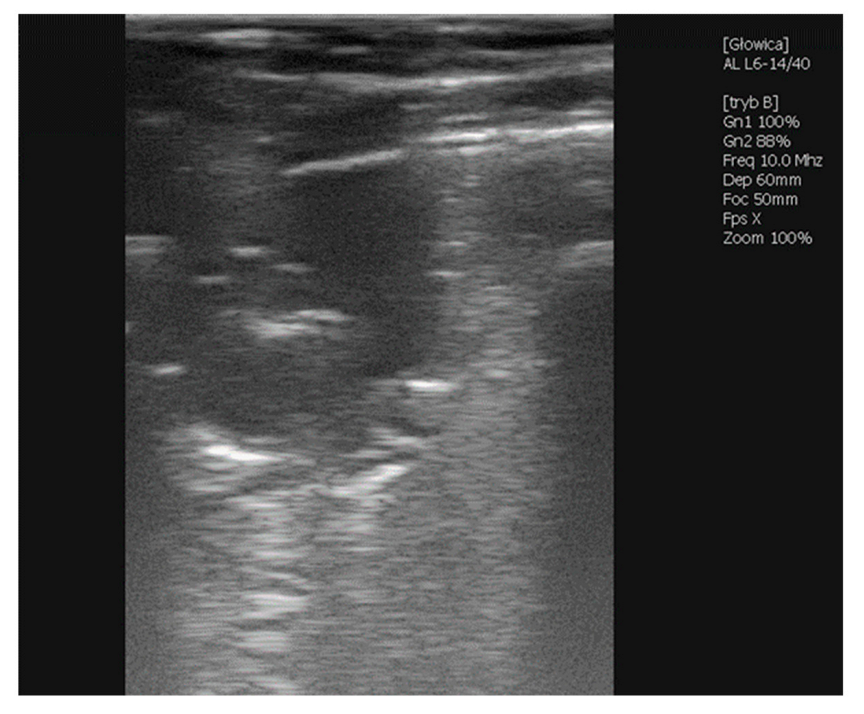

2.1.5. Case 3—Suspicion of Extrapulmonary Disorders